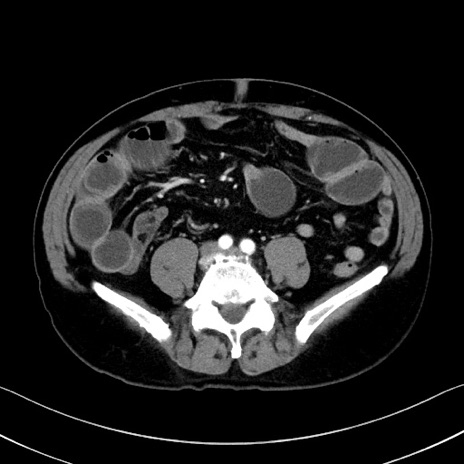

症例35(横断像)

【症例】70歳代 男性

【主訴】腹部膨満、嘔吐

【現病歴】昨日より腹部膨満感出現。本日増悪し、仙痛出現。嘔吐あり、受診。

【既往歴】糖尿病、胆摘後

【身体所見】BP 149/80mmHg、HR 74/min、BT 35.9℃、腹部:膨満、軟、圧痛なし。腸雑音減弱あり。上腹部正中切開瘢痕あり。

【データ】WBC 13500、CRP 1.72